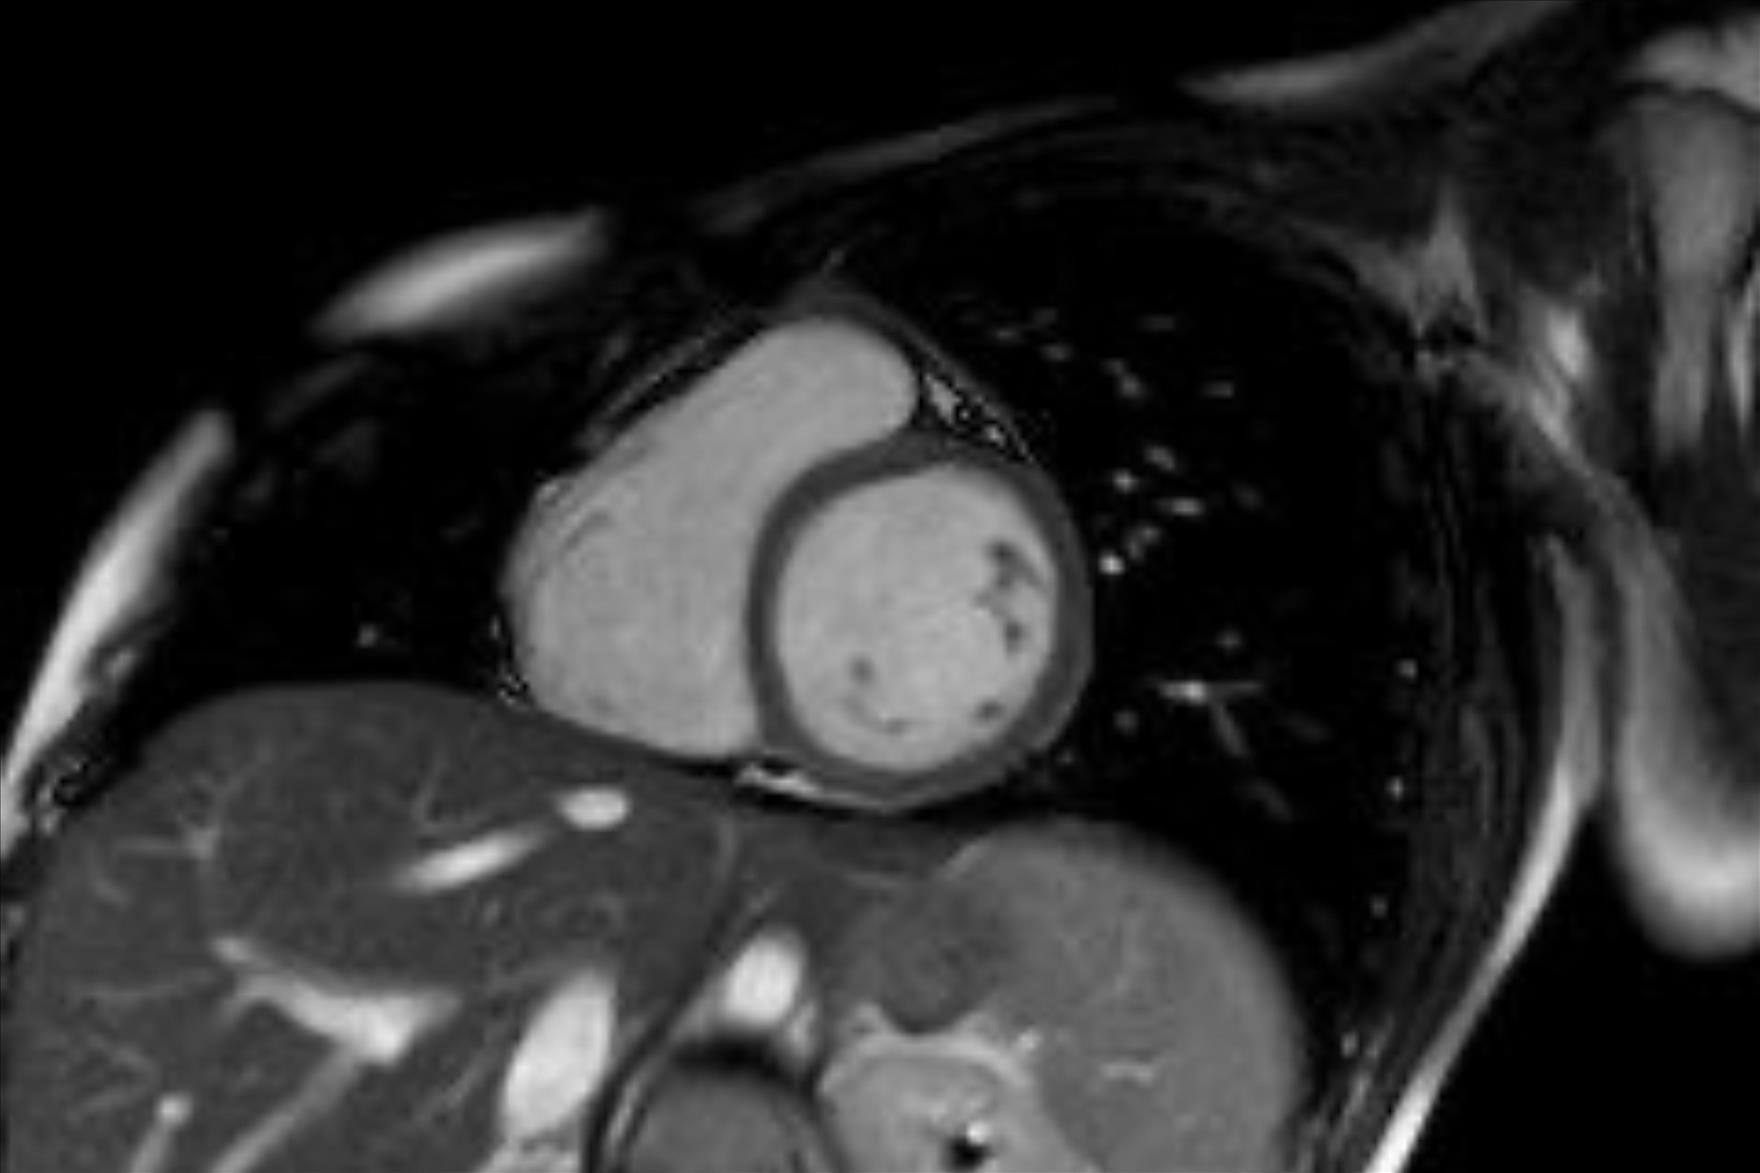

Bu yöntemin hastada kalp hastalığı, damar tıkanıklığı, akciğer hastalığı veya kanser gibi önemli durumların varlığını veya yokluğunu göstermesi açısından büyük fayda sağladığına değinen Doç. Dr. Vefa Çakmak sözlerine şöyle devam etti: “Özellikle sigara kullanan bireylerde, akciğerin bu durumdan ne derece etkilendiği açıkça görülebiliyor. Böylece, sigara bağımlılarının sıkça sorduğu ‘Acaba kanser miyim?’ sorusuna yanıt bulunmuş oluyor. Uygulamanın herhangi bir zararı bulunmuyor ve kullanılan teknoloji uluslararası standartlara uygun şekilde çalışıyor. Kalp hastalıklarının tanısında bir diğer önemli yöntem olan Kardiyak MR ise, anjiyografi ile tanı konulamayan durumlarda devreye giriyor. Kalp duvarlarının yapısal hastalıkları, kalp kapakçıklarıyla ilgili problemler, demir birikimi gibi daha özel durumların tanı ve takibi için tercih ediliyor. Bu yöntemde radyasyon bulunmuyor. Yaklaşık 25–30 dakika süren bu görüntüleme sırasında hastanın üzerindeki metal eşyalar çıkarılıyor, monitörize ediliyor ve nefes tutma komutlarına uyumu sağlanıyor. Çekim, ilgili hekim istemi doğrultusunda gerçekleştiriliyor ve sonuçlar genellikle bir iş günü içinde hastaya ulaştırılıyor. Hem BT hem de Kardiyak MR görüntülemeleri, uzman ekipler tarafından gerçekleştiriliyor ve elde edilen veriler, tanı sürecinde oldukça değerli bilgiler sunuyor. Bu teknolojiler sayesinde, birçok hastalık erken dönemde saptanabiliyor; gereksiz girişimlerin önüne geçiliyor ve hasta güvenliği en üst düzeyde tutuluyor.”